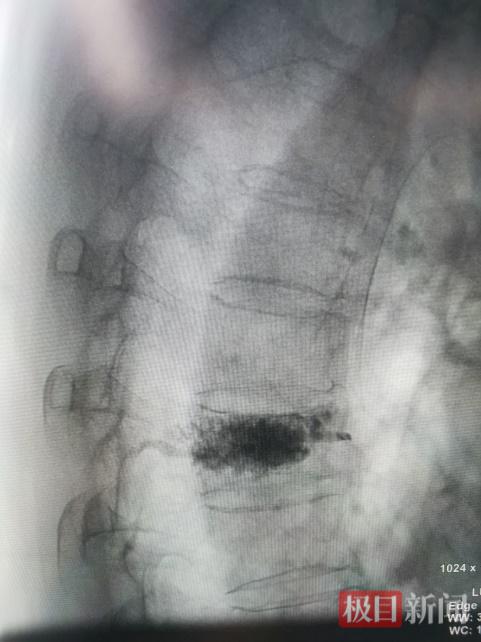

术后影像显示,骨水泥在骨折椎体内均匀分布

2月15日,在C臂机的精准引导下,梅红军团队精准完成手术,全程顺利,出血量极少。这项技术通过仅几毫米的微小切口,在影像引导下将医用“骨水泥”精准注入受损椎体,如同给塌陷的“房子”重新注入“支撑梁”,快速稳定骨折、缓解疼痛,并确保脊髓神经功能不受损伤。